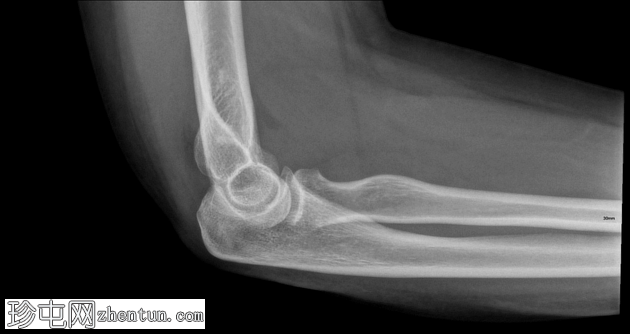

侧位

侧位片显示前后脂肪垫征,提示关节囊扩张。

可见桡骨头轻微凹陷性骨折。

桡骨头骨折通常由肘关节伸直时手掌撑地摔倒所致。侧位X线片上前后脂肪垫征的存在是关节囊扩张(由关节积血和关节积液引起)的重要间接指标,即使皮质骨未见明显损伤,也是隐匿性骨折的标志